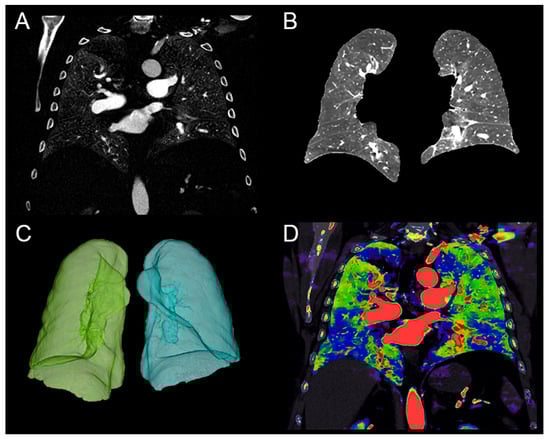

2.3. Quantitative Perfusion Blood Volume (PBV)

2.4. Per-Segment Qualitative Analysis of the PBV